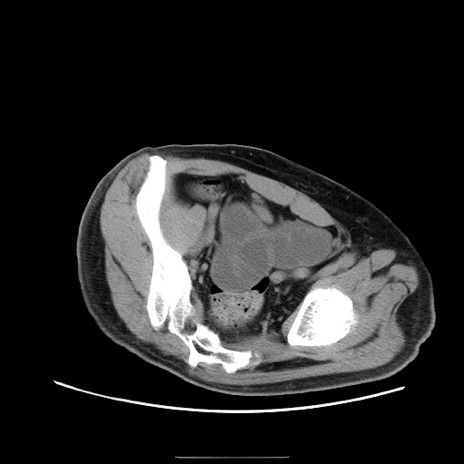

症例22(横断像)

【症例】50歳代男性

【主訴】腹痛

【現病歴】AVMからの被殻出血のため回復期リハ病棟入院中。 本日午後3時頃急に下腹部痛が出現した。

【既往歴】AVM、被殻出血、虫垂炎、高血圧

【身体所見】意識晴明、左半身不全麻痺、会話の理解は良好、36.5°C、腹部:膨隆、全体に板状硬、下腹部正中に圧痛点あり、反跳痛-、筋性防御不明、右下腹部にope scar

【データ】WBC 9400、CRP 0.06